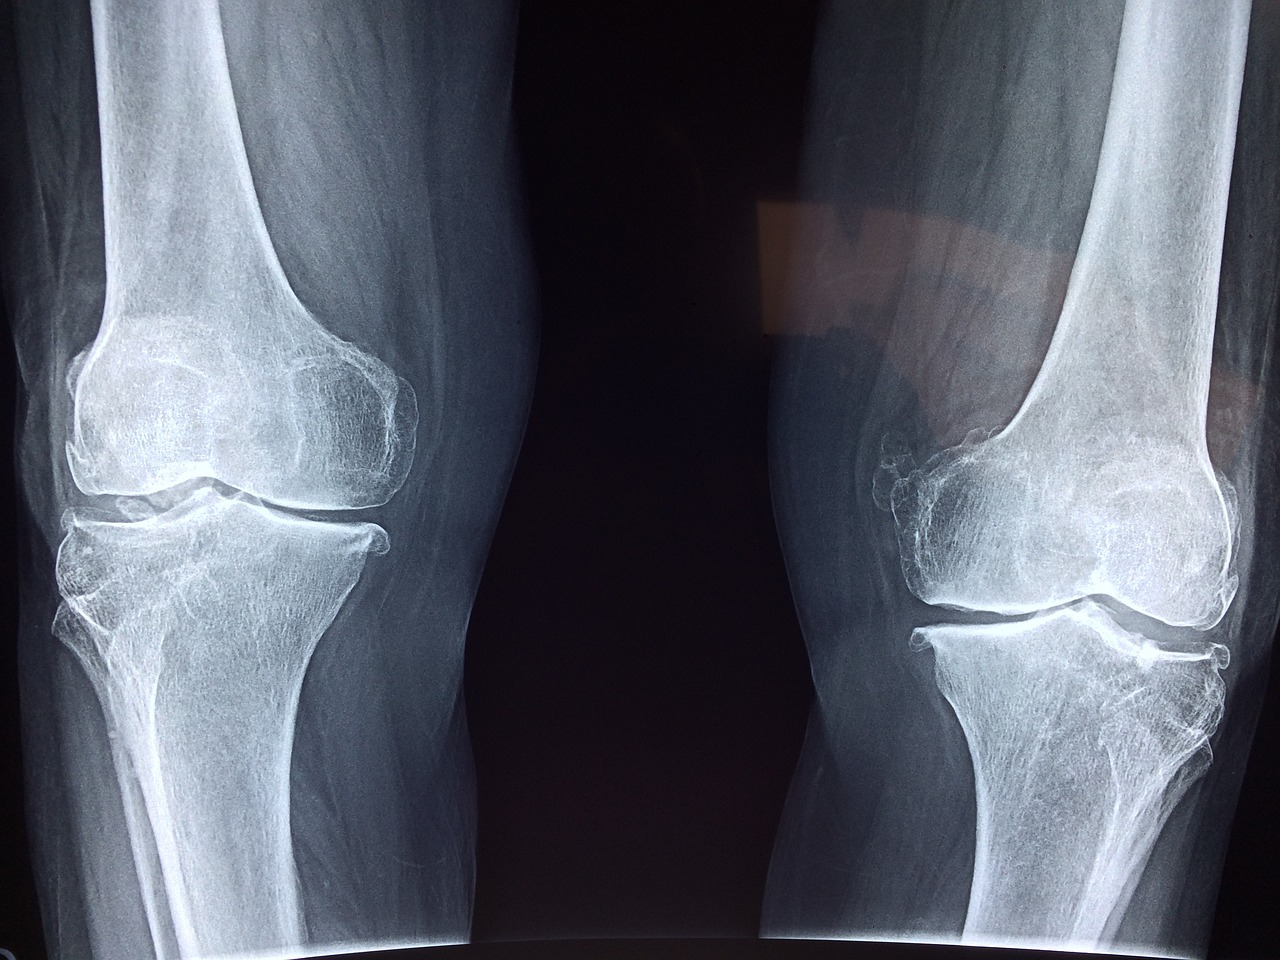

1️⃣ 무릎 인공관절 수술 후 정상적인 회복 과정

✅ 무릎 인공관절 수술 후엔 어느 정도의 통증과 부기가 따라오는 것이 일반적입니다.

수술 부위 조직이 회복되는 동안 통증은 보통 2~6주 사이 점차 줄어들며,

무릎의 운동 범위도 점점 회복되게 됩니다.

● 수술 후 12주차: 통증은 있지만 움직임이 늘고 실밥 제거, 간헐적 얼음찜질 권장

● 3~6주차: 가벼운 재활운동 시작, 계단이나 평지 보행이 가능해짐

● 6주차 이후: 통증과 부기 대부분 감소, 관절 기능이 일상생활 수준으로 회복

💡 이 시기에도 통증이 점점 심해지거나 다시 부어오른다면 ‘무릎 인공관절 수술 후 염증’ 가능성을 꼭 생각해봐야 합니다.